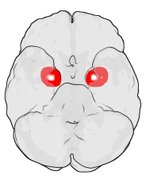

Location of the amygdalae in the human brain

The amygdalae (/əˈmɪɡdəl/; singular: amygdala; also corpus amygdaloideum; Latin, from Greek ἀμυγδαλή, amygdalē, 'almond', 'tonsil',[1] listed in the Gray's Anatomy textbook as the nucleus amygdalæ) are almond-shaped groups of nuclei located deep within the medial temporal lobes of the brain in complex vertebrates, including humans.[2] Shown in research to perform a primary role in the processing of memory and emotional reactions, the amygdalae are considered part of the limbic system.[3]